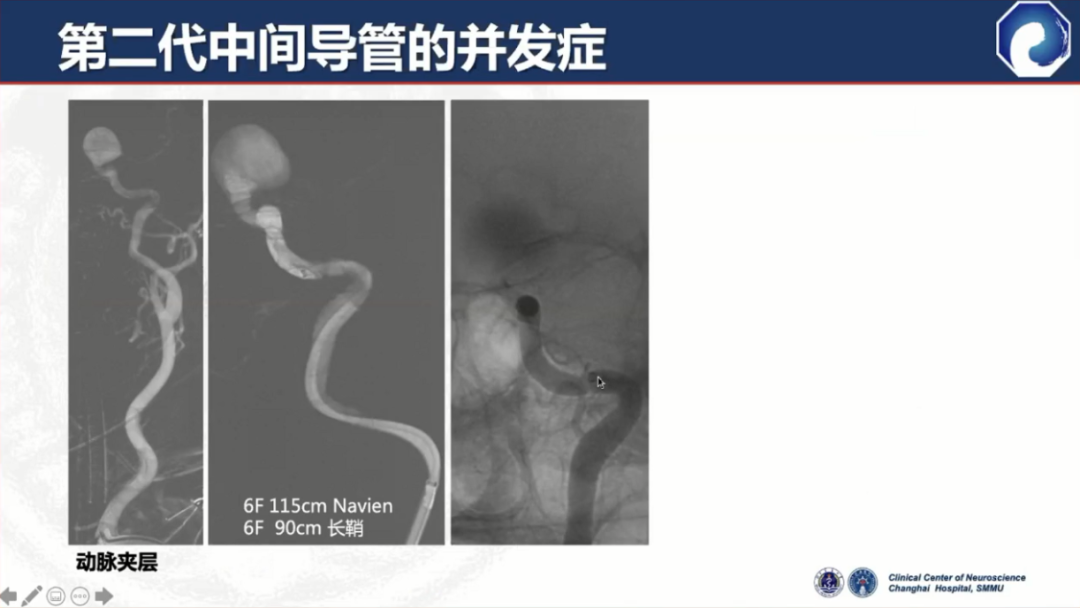

第二代中间导管仍存在血管内夹层等并发症,这也是所有导管都存在的问题。

此外,中间导管的支撑力比较差,近端需加长鞘或8F Guiding做支撑,需三轴系统